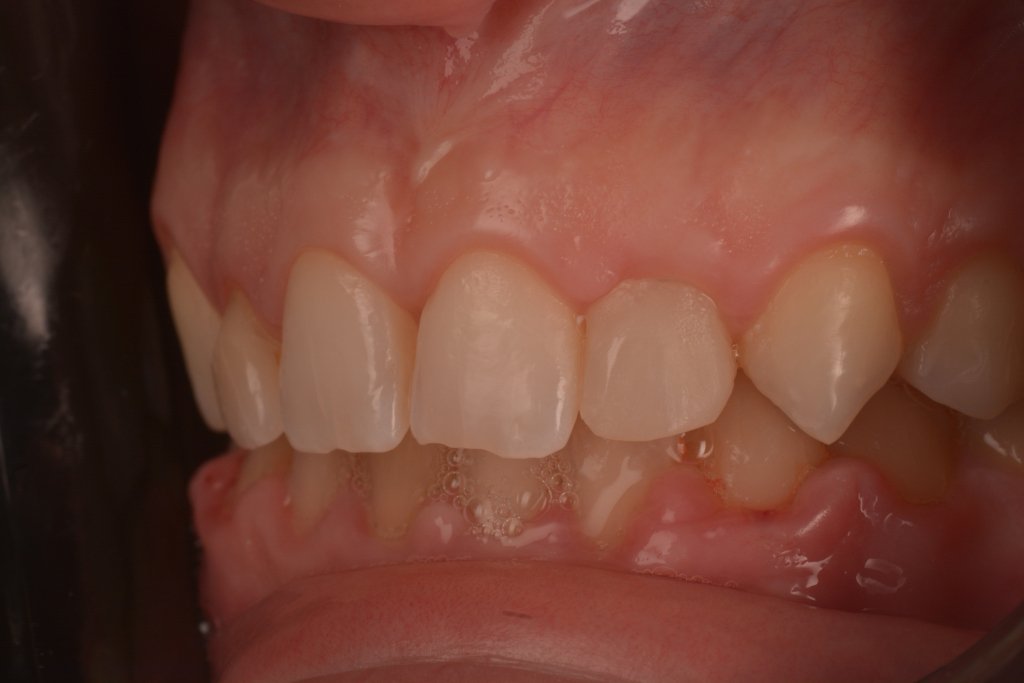

2 SEMANAS DESPUÉS

No me asusta esta ligera inflamación, al revés se que están pasando cosas buenas, la encía se esta estabilizando y engordando según los principios de la técnica BOPT. Así que tengo tiempo para disfrutar simplemente del trabajazo de Nacho.